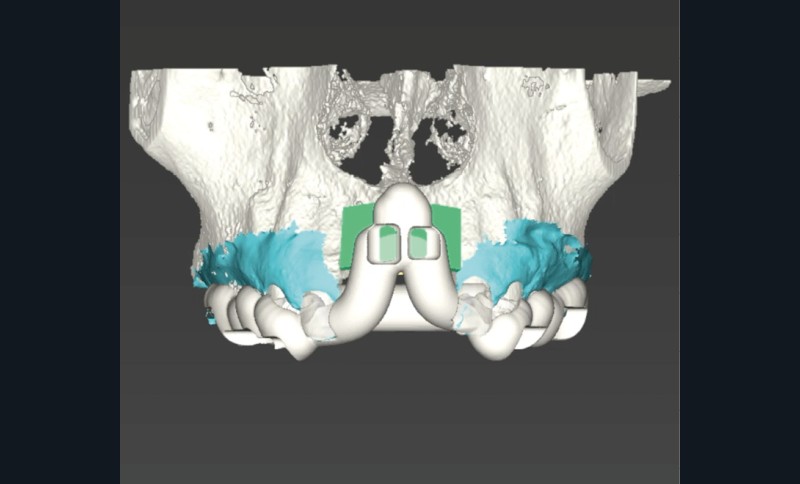

L’avènement des technologies numériques a permis d’améliorer la précision de ces procédures. La planification implantaire 3D, associée à la conception et fabrication assistée par ordinateur (CAD/CAM), permet aujourd’hui de concevoir des guides chirurgicaux spécifiques optimisant et sécurisant le positionnement des blocs osseux. De même, la démocratisation récente des techniques de chirurgie guidée dynamiques par caméra stéréoscopique constitue un outil attractif pour les techniques de reconstruction osseuse. Ainsi, la taille du bloc à prélever sur la zone rétromolaire mandibulaire peut aussi être exactement déterminée en amont de la chirurgie (fig. 1 et 2).

La possibilité de réaliser le prélèvement osseux en bloc avec un guide statique permet d’affiner sensiblement la quantité d’os prélevée en fonction du besoin réel et diminuer la morbidité du geste. En revanche, le positionnement même du guide nécessite l’ouverture d’un lambeau de grande taille.

La chirurgie guidée dynamique permet, quant à elle, de prélever par piezochirurgie (Piezotouch, Mectron) de façon naviguée (fig. 3). Ainsi, le bloc peut être designé en amont sur le logiciel de planification implantaire pour correspondre parfaitement au défaut osseux en présence, et prélevé à l’identique sur la ligne oblique externe (fig. 4 à 8).